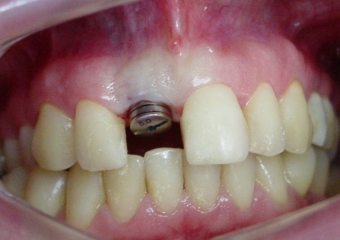

Imagem de um implante com cicatrizador e com o dente provisório removido.